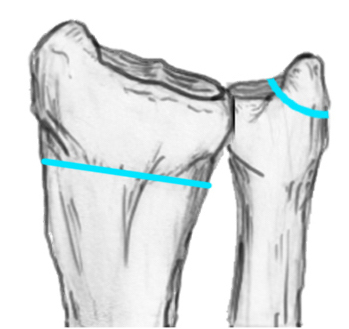

Distal Radius Angles

- radial volar tilt 11°

- radial inclination  22°

- radius is 11 mm longer than ulna

- ulna variance 2mm positive on average

Distal Radius NormalNormal Radial InclinationNormal Radial Length